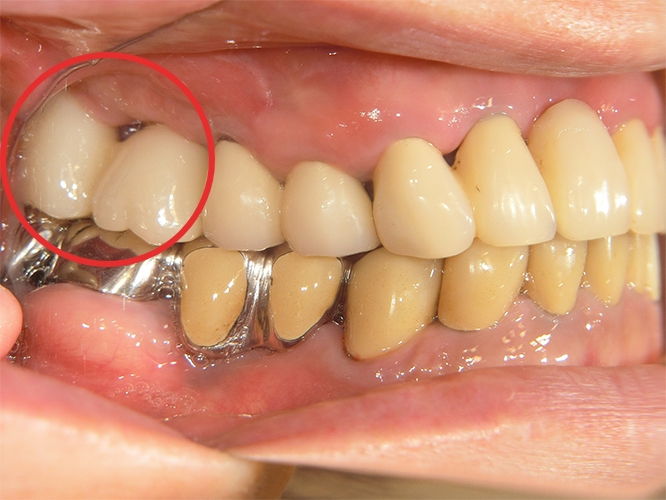

上部構造装着後のレントゲンと口腔内写真